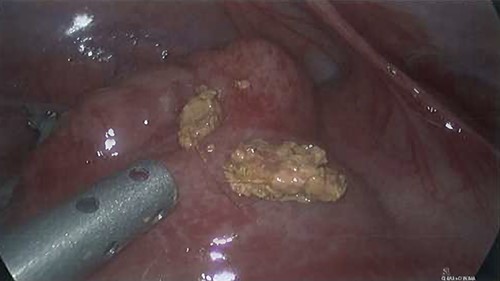

The patient proceeded to laparoscopic appendicectomy. At the outset of the procedure a cluster of short, firm, light coloured hairs were removed from the umbilicus. These hairs were different to the patient’s own and appeared like animal hair. Intra-operatively, the appendix was found to be inflamed with a perforated base (Fig. 3). Faecoliths, containing a large volume of hairs identical to those found in the umbilicus, had escaped the appendix through the perforation (Fig. 4). Pus was identified in all four quadrants of the abdomen. After dissection of the meso-appendix, a partial caecectomy was performed using a laparoscopic stapler. The hairs were carefully removed, and the abdomen was irrigated. A drain was placed in the pelvis.

Axial CT image demonstrating the inflamed appendix containing hyperdensities.